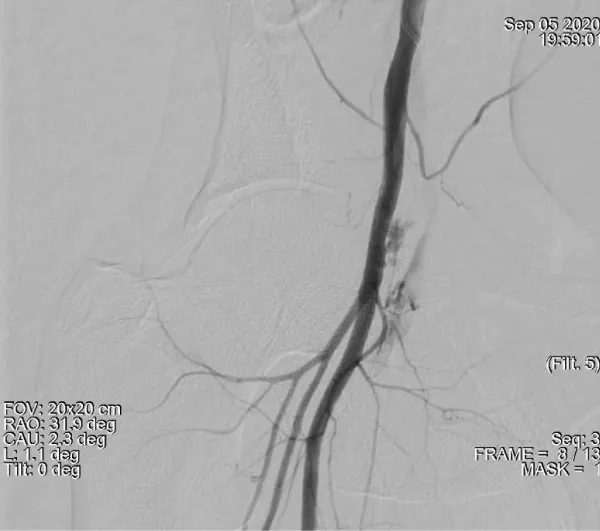

A 51-year-old male, nondiabetic with a history of angina on exertion and strongly positive exercise stress test for reversible myocardial ischemia with normal LV systolic function underwent left heart cardiac catheterization. He was found to have significant coronary artery disease (LAD/D1 true bifurcation lesion and significant stenosis in the proximal to mid circumflex artery. A 2.5 x 33 mm Xience stent (Abbott Vascular) was deployed in Left Circumflex artery. PCI to LAD/D1 true bifurcation was done with DK crush technique with a 3 x 38 mm Xience stent (Abbott Vascular) in LAD and 2.5x 18 mm Xience stent (Abbott Vascular) in D1 with good angiographic results. Aspirin and Ticagrelor were used as an antiplatelets. Intravenous antiplatelet were not given. Right common femoral arterial access was used which was a difficult puncture with three attempts. Right femoral venous access was also taken (single attempt). The patient was sent back to the coronary care unit with the instruction of removal of both femoral sheaths when activated clotting time (ACT) is less than 180 seconds and to be followed by manual compression and a tight pressure bandage to prevent hematoma. Thirty minutes after the procedure, the patient became hypotensive (systolic BP 70 mmHg) with bradycardia (heart rate: 36 beats/min) and treated as vasovagal syncope with atropine and Intravenous fluid. There was continuous blood oozing from sides of arterial sheath and from another arterial puncture site which was not responding to manual compression so both sheaths were removed in order to have more effective manual compression. Total one-hour manual compression given which led to no ooze in right groin even on coughing and then a compression bandage done. He have two more episodes of hypotension in next one hour in spite of rapid intravenous fluid transfusion. So inotropes with noradrenaline infusion was also initiated but blood pressure remained borderline. He was feeling fatigue and dizzy. Reinspection of right groin showed hemorrhagic bluish discoloration with scrotal swelling. The hemoglobin concentration fell from 15.1 (preprocedure Lab value) to 10.5 (ABG value) grams/deciliter. A CT angio scan of the abdomen and groin arteries showed a retroperitoneal and intraperitoneal hematoma with extravasation of contrast from right common femoral artery in to surrounding soft tissue suggestive of active leak of contrast, extending in the subcutaneous tissue in groin and lower right inguinal region (Figure 1). The patient was transferred back to the cardiac Cath lab because of persistent hypotension despite fluid resuscitation. Left common femoral arterial access was obtained and a 6 French sheath was introduced. A Judkins right (JR6) diagnostic catheter was passed retrogradely into the left common iliac artery and then antegradely into the right iliofemoral arterial system over a 0.035 inch guide wire. Digital subtraction angiography (DSA) showed the location of the retroperitoneal hematoma (RPH) (Figure 2).

Figure 2: Demonstrates a large amount of extravascular contrast with the right iliac angiogram location near the middle third of the femoral head. suggestive of active bleeding from mid right common femoral artery into the pelvis.